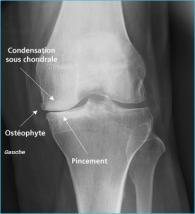

Le diagnostic d’arthrose est envisagé par le médecin devant des douleurs, une difficulté à effectuer des mouvements articulaires, une gêne à la marche, un gonflement (ou une déformation) d’une articulation. Mais, seule la radiographie de l’articulation en montrant des images caractéristiques peut confirmer le diagnostic. La douleur est le principal symptôme.

•une éventuelle augmentation de volume du genou en rapport avec la présence de liquide dans l’articulation. Les radiographies révèlent des images caractéristiques d’arthrose :

•pincement de l’interligne articulaire (diminution de l’espace qui sépare les 2 os composant l’articulation) ;

•modifications de la structure de l’os situé immédiatement sous le cartilage ; •expansions osseuses à la jonction entre l’os et le cartilage (becs de perroquet ou ostéophytes).